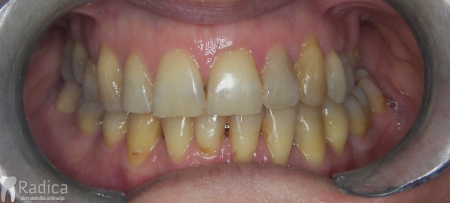

Danas je sve veći broj odraslih pacijenata u terapiji. Pod „odraslim pacijentom“ u ortodonciji se smatraju svi pacijenti koji su završili rast i razvoj – prosječno nakon 18 – 20 godine života. Kako se sa starenjem smanjuje broj stanica i prokrvljenost koštanog tkiva terapija obično traje duže i retencija je doživotna. Također, kako veći broj pacijenata dolazi s već izgubljenim zubima, abradiranim (potrošenim) zubima i poremećenom okluzijom, očekivanja od ortodontske terapije trebaju biti realna, a ne idealna.

Dakle, poslagat ćemo zube koje imamo, osigurati okluziju, stvoriti prostor za nadoknadu nekih zuba i samim tim spriječiti daljnje propadanje zuba i zagriza ali rezultat će biti „realan“ i daleko od onog idealnog rezultata kojeg možemo postići kod mladih osoba koje imaju sve zube.

Međutim, jedan od uzroka parodontitisa je loš položaj zuba i posljedično loš zagriz. Kod lošeg zagriza opterećenje zuba prilikom žvakanja je patološko. Zub nije opterećen po njegovoj dužinskoj osi – što ga štiti od oštećenja – nego je opterećen drugačije. Uslijed toga dolazi do naginjanja zuba, gubitka kosti, povlačenja zubnog mesa i ogoljenja korijena zuba.

U galeriji slika su prikazani klinički slučajevi ovakvih odraslih pacijenta bilo da se radi samo o ortodontskoj terapiji ili predprotetskoj ortodonciji.